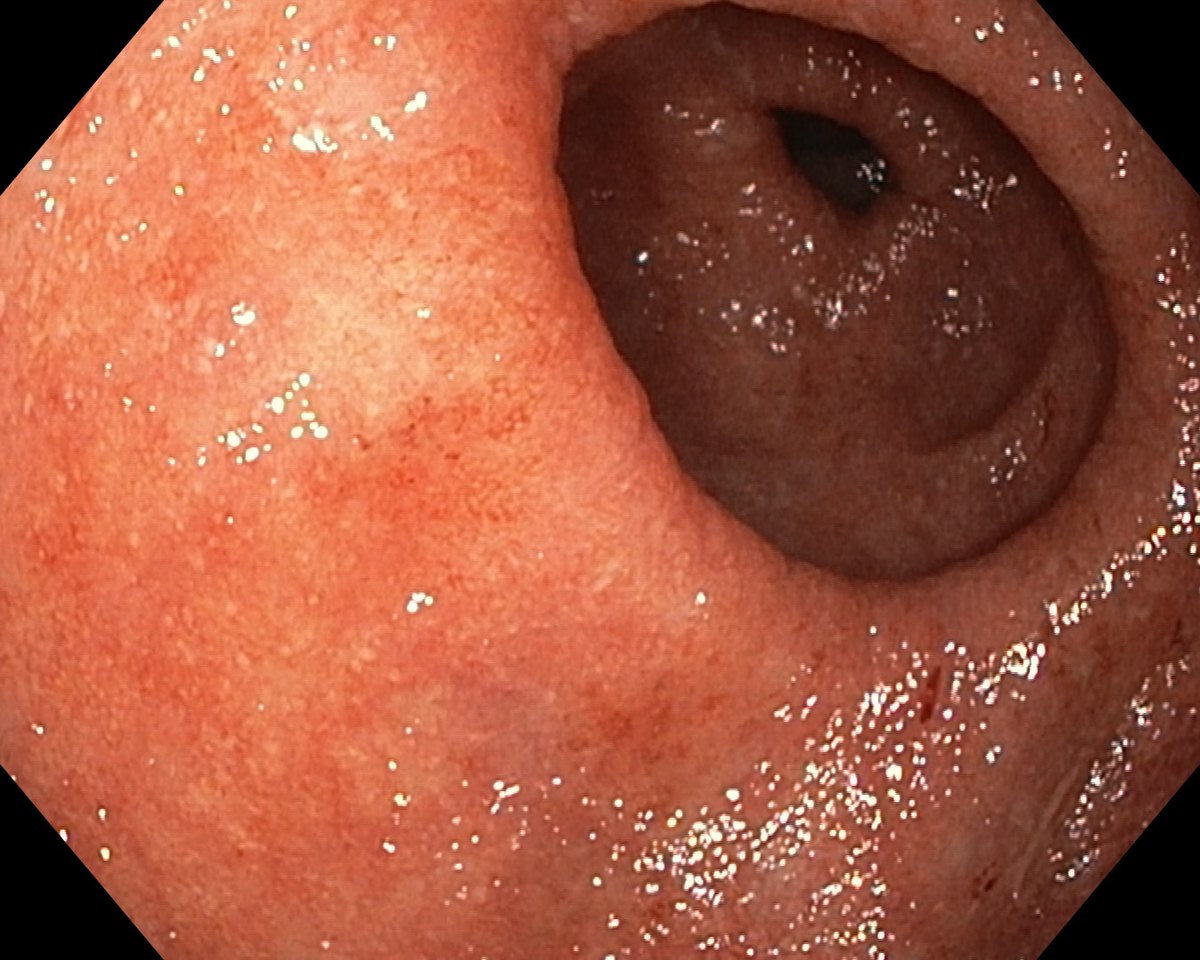

A Distal Ulcerative Colitis, Proctosigmoiditis Ulcerosa

A Distal Ulcerative Colitis.

A Distal Ulcerative Colitis